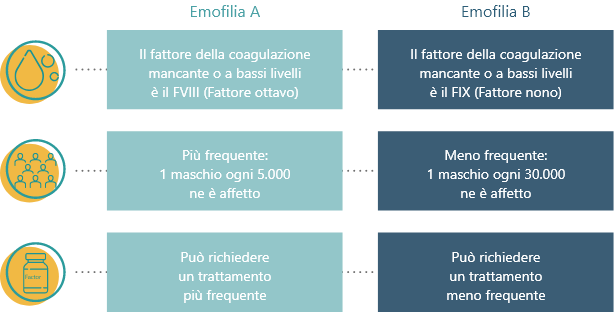

L’emofilia è una rara malattia emorragica che riduce la capacità del sangue di coagulare ed è ereditaria, ovvero trasmessa attraverso i geni.

L’emofilia è causata da fattori di coagulazione nel sangue mancanti, inattivi o presenti a bassi livelli.

Esistono due forme di emofilia:

La gravità dell’emofilia è determinata dalla quantità del fattore della coagulazione presente nel sangue: livelli più bassi di fattore equivalgono a una forma di emofilia più grave.